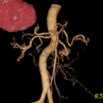

Abd Aorta VR

从外形上显示腹部主动脉及其主要分支血管的起源.走形及其它的形态

Liver Mass & Abd Aorta VR

占位性病变与腹主动脉及其主要分支血管的VR图像:显示占位性病变与其周围血管的相应关系